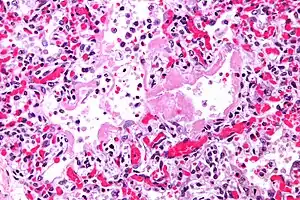

| Micrograph of diffuse alveolar damage, the histologic correlate of acute interstitial pneumonitis. H&E stain. | |

Rapid progression from initial symptoms to respiratory failure is a key feature. An X-ray that shows ARDS is necessary for diagnosis (fluid in the small air sacs (alveoli) in both lungs). In addition, a biopsy of the lung that shows organizing diffuse alveolar damage is required for diagnosis. This type of alveolar damage can be attributed to nonconcentrated and nonlocalized alveoli damage, marked alveolar septal edema with inflammatory cell infiltration, fibroblast proliferation, occasional hyaline membranes, and thickening of the alveolar walls. The septa are lined with atypical, hyperplastic type II pneumocytes, thus leading to the collapse of airspaces. Other diagnostic tests are useful in excluding other similar conditions, but history, X-ray, and biopsy are essential. These other tests may include basic blood work, blood cultures, and bronchoalveolar lavage. The clinical picture is similar to ARDS, but AIP differs from ARDS in that the cause for AIP is not known.

Acute interstitial pneumonia (AIP)/Idiopathic DAD -

Acute interstitial pneumonia (AIP)/Idiopathic DAD